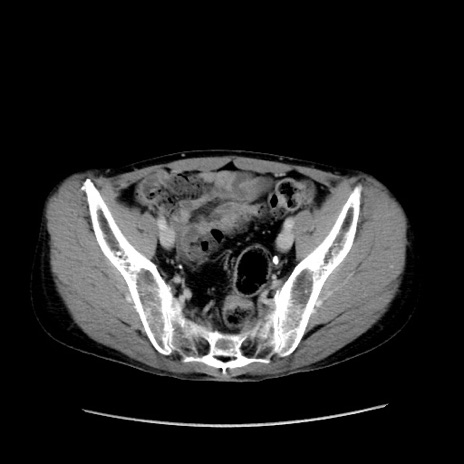

冠状断像

症例37(横断像)

【症例】40歳代 男性

【主訴】腹痛

【現病歴】4時間ほど前に電車に乗車中に臍部上より腹痛出現。徐々に増悪し起立困難となり、救急外来受診。生ものは数日食べていない。今朝お雑煮を食べた。

【身体所見】BT 36.8℃、BP 117/84mmHg、HR 91/min、SpO2 97%、苦悶様、腹部:臍上部広範囲圧痛あり、反跳痛±

【データ】WBC 8100、CRP 0.03